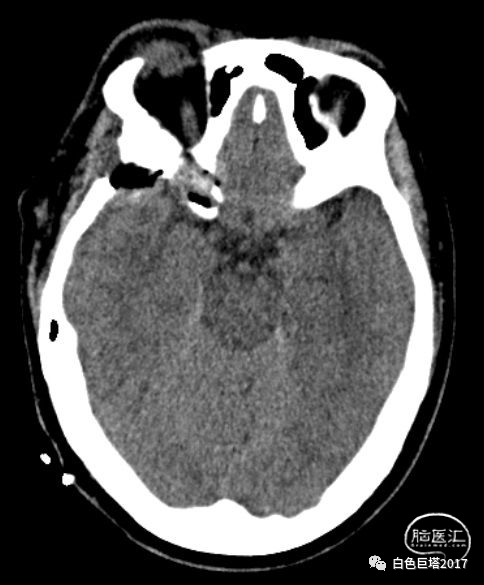

术后复查头颅CT

CT重建可见患者预定骨质磨除满意。

下图红箭头所示为磨除后的视神经管。